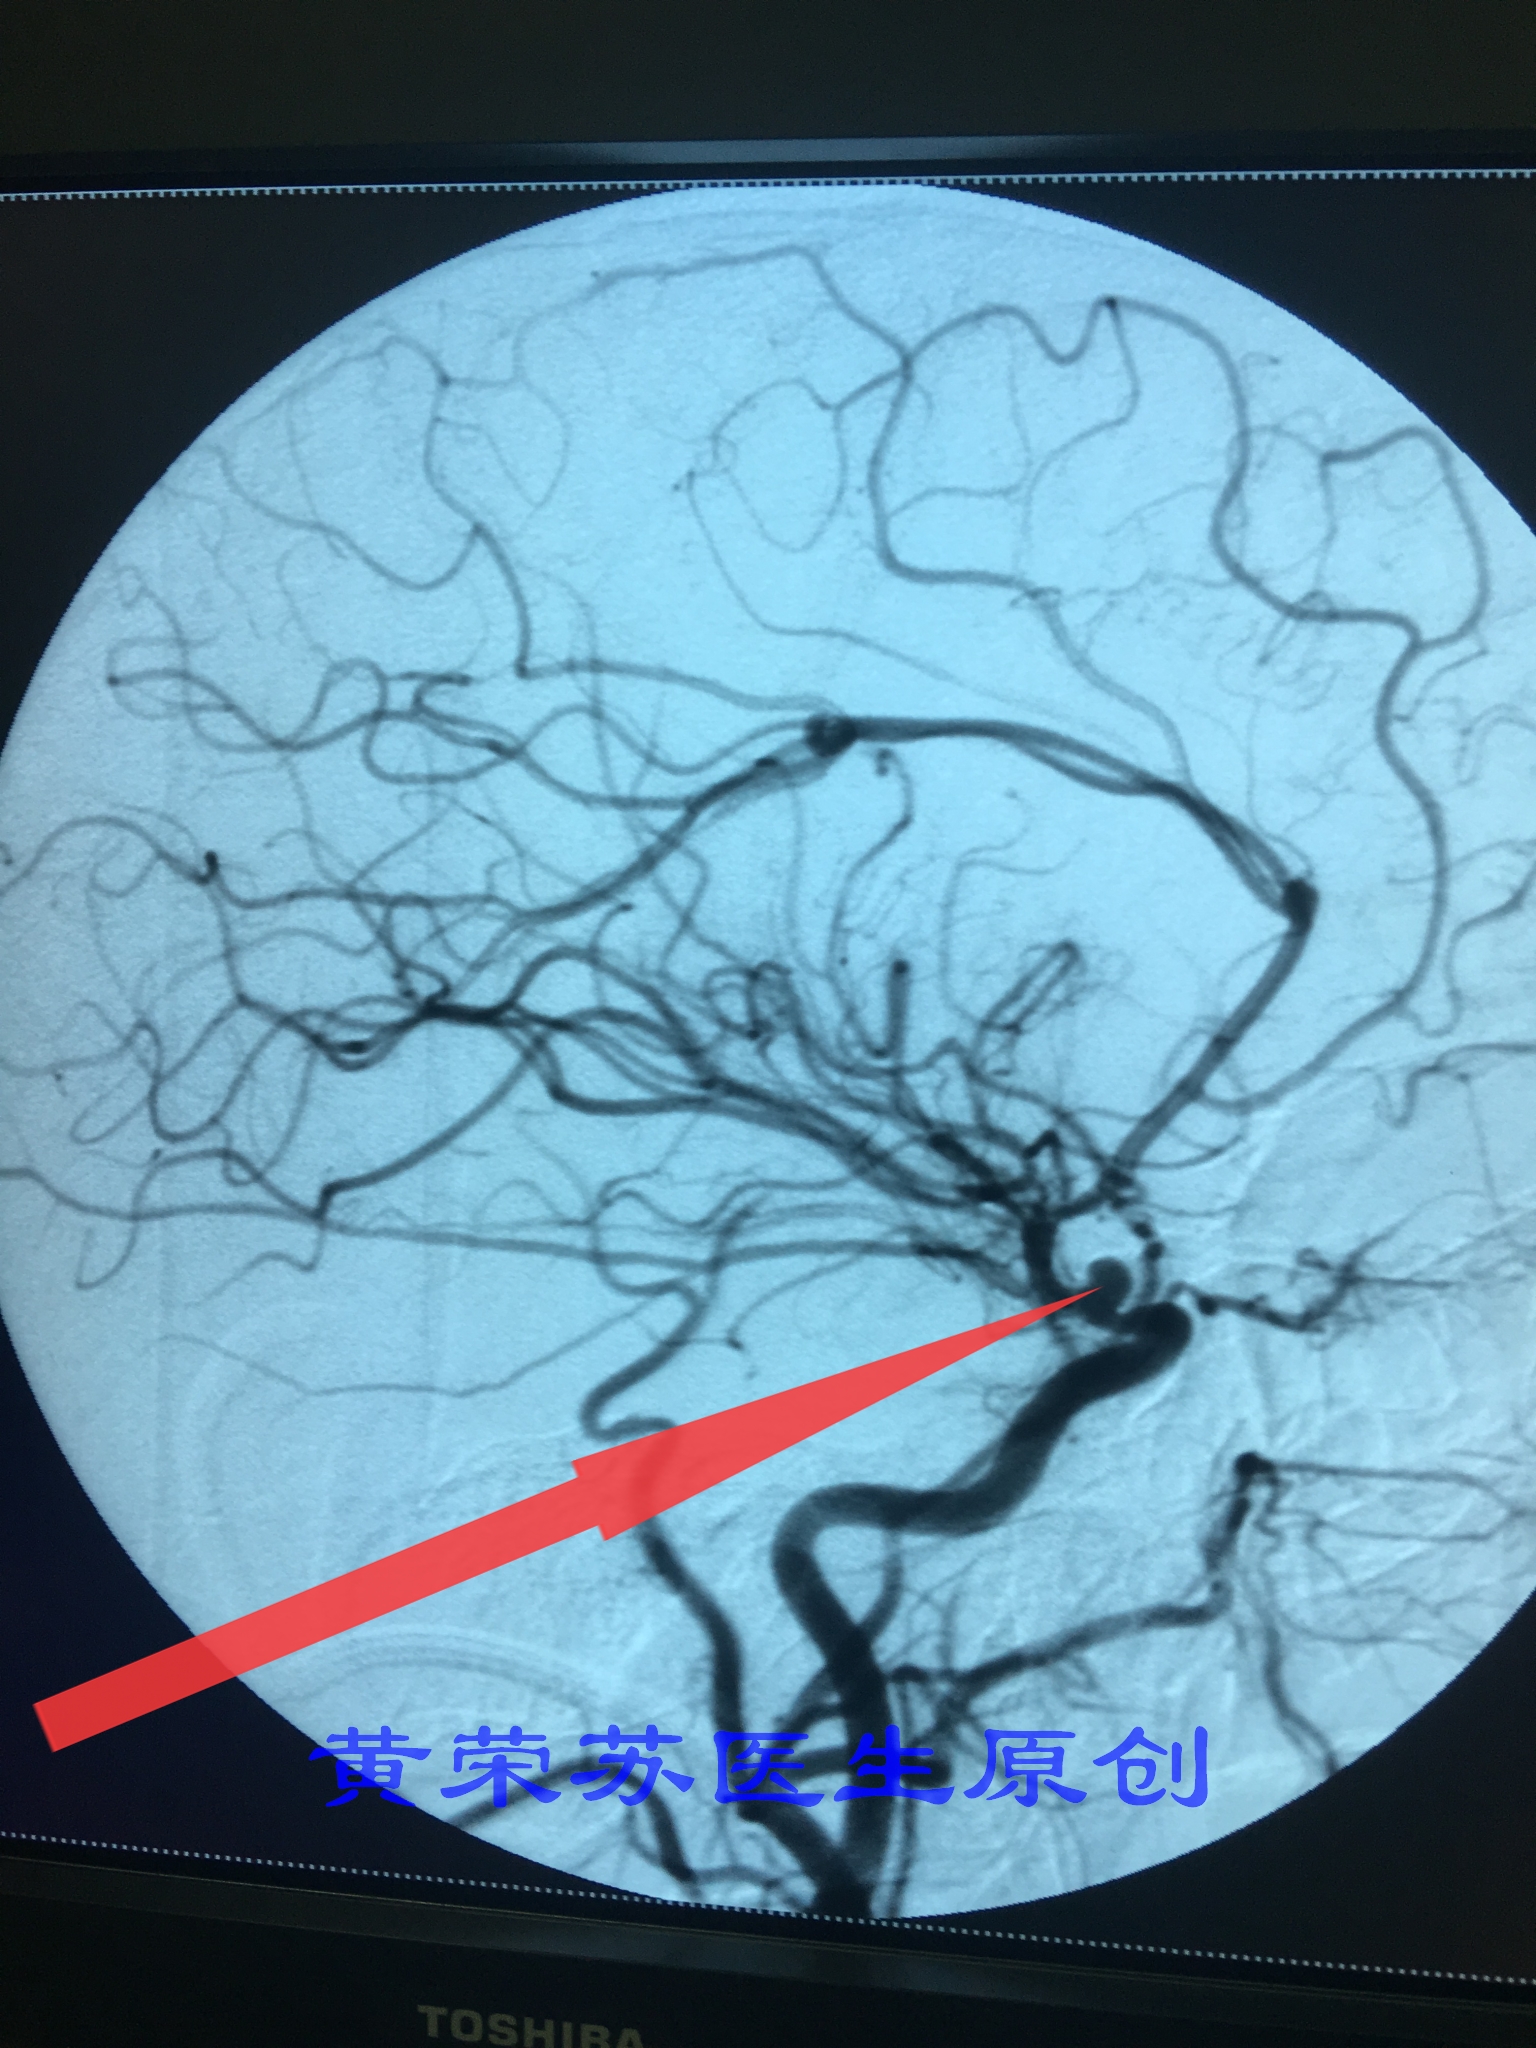

5、动脉瘤破裂出血:起病急,进展快,死亡率仅次于脑干出血。因此动脉瘤诊治目前提倡早发现、早治疗,及早拆除颅内的“定时*弹炸**”。动脉瘤未破裂之前可以进行脑血管介入栓塞治疗。

图六、脑血管造影检查提示动脉瘤